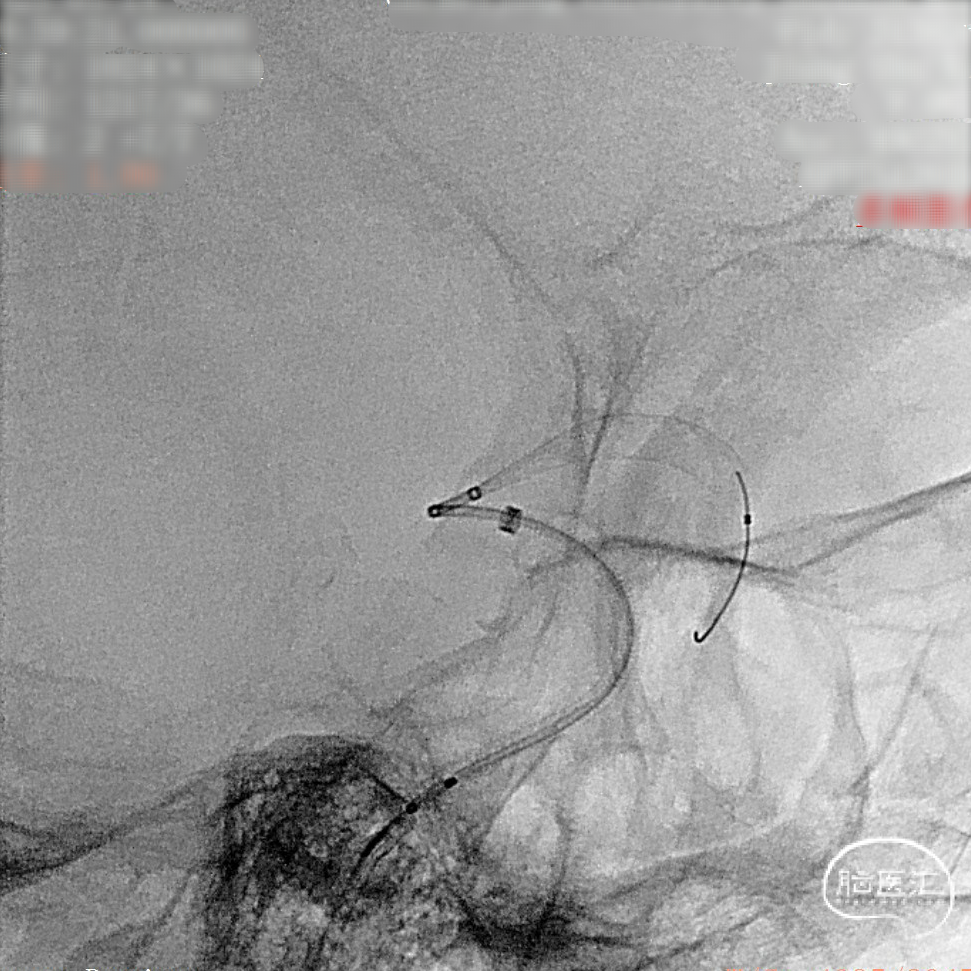

支架完全释放。

造影明确打开贴壁满意。

正侧位造影:支架放置后可见动脉瘤内造影剂明显滞留。

大动脉瘤的微创介入栓塞治疗存在需要支架辅助,瘤颈处理困难、复发率高、费用高等难点;血流导向密网支架置入是较优选择,操作相对简单,不用填塞弹簧圈,完整覆盖瘤颈,远期明显降低再复发概率。本病例为右侧颈内动脉C7段累及脉络膜前动脉的大动脉瘤,该部位解剖结构复杂,周围血管分支多,在操作过程中要避免损伤正常血管,否则会引发严重脑缺血事件;其次,动脉瘤与脉络膜前动脉关系密切,既要处理好动脉瘤,又要保证脉络膜前动脉的血供不受影响,这对手术操作精度要求较高;再者,瘤颈的处理较为棘手,瘤颈较宽,传统弹簧圈栓塞难以达到理想效果,且容易复发。血流导向密网支架置入可解决这些问题,术前需借助3D-DSA,全面评估动脉瘤大小、形态、瘤颈宽度、与周围血管关系,制定精准手术方案。操作时,微导管的到位是关键一步,要在路径图引导下,小心、轻柔操作,避免刺激血管引发痉挛或动脉瘤破裂。释放支架过程中,要注意关注支架位置和贴壁情况。释放后要通过多角度造影,确认支架完全覆盖瘤颈,且支架内血流通畅,分支血管未受影响。同时,术后要密切观察患者神经功能变化,预防血栓形成、血管痉挛等并发症,及时给予抗血小板、解痉等药物治疗。